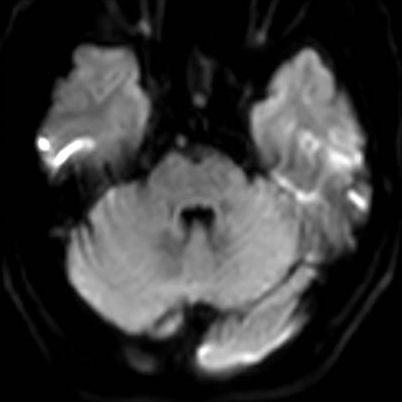

急诊头颅DWI梗死灶还尚未显影

卒中中心迅速反应,启动绿色通道。急诊头颅CT可见脑干梗死灶。患者在静脉溶栓时间窗内,急诊行静脉溶栓,同时急诊头颅MRA可见基底动脉闭塞,DWI上还尚未显影。如果救治不及时,基底动脉闭塞很可能引起脑干、小脑大面积脑梗死从而危及生命。